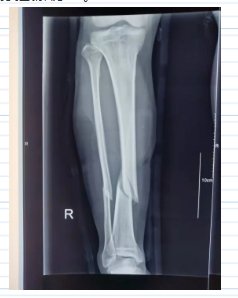

患者李某,男,37岁,因“摔伤致右小腿疼痛约两小时”于2021年9月20日13:09来诊,平车推行入院。缘患者2021年9月20日约11点,在工作时从约两米高处梯子上失足摔伤致右小腿疼痛不适,肿胀,活动障碍,无右下肢感觉异常,无头晕、恶心呕吐,无心悸、胸闷,由他人送至我院急诊外科就诊查x片提示“右胫腓骨中下段骨折”,为进一步治疗而收住院,入院诊断为:“1.右胫骨骨折 2.右腓骨骨折 3.左肘挫擦伤”。

入院后杨为民副总院长查看病人后诊断该患者为:“1.右胫骨骨折 2.右腓骨骨折 3.左肘挫擦伤”,指示先予完善相关辅助检查,患肢夹板及肢具外固定,吸氧、心电监护,密切观察病情变化,经充分抗炎对症消肿治疗后,做好术前准备。于2021年9月20日14:30送手术室在腰硬联合麻下、C臂机下行“右胫骨骨折闭合性复位空心髓内钉内固定术+右腓骨骨折闭合性复位弹性髓内钉内固定术”手术取得圆满成功。该术式手术创伤小,外观美观,术后恢复快。术后患者在外科病区团队精心护理及康复治疗下,患者恢复情况良好。